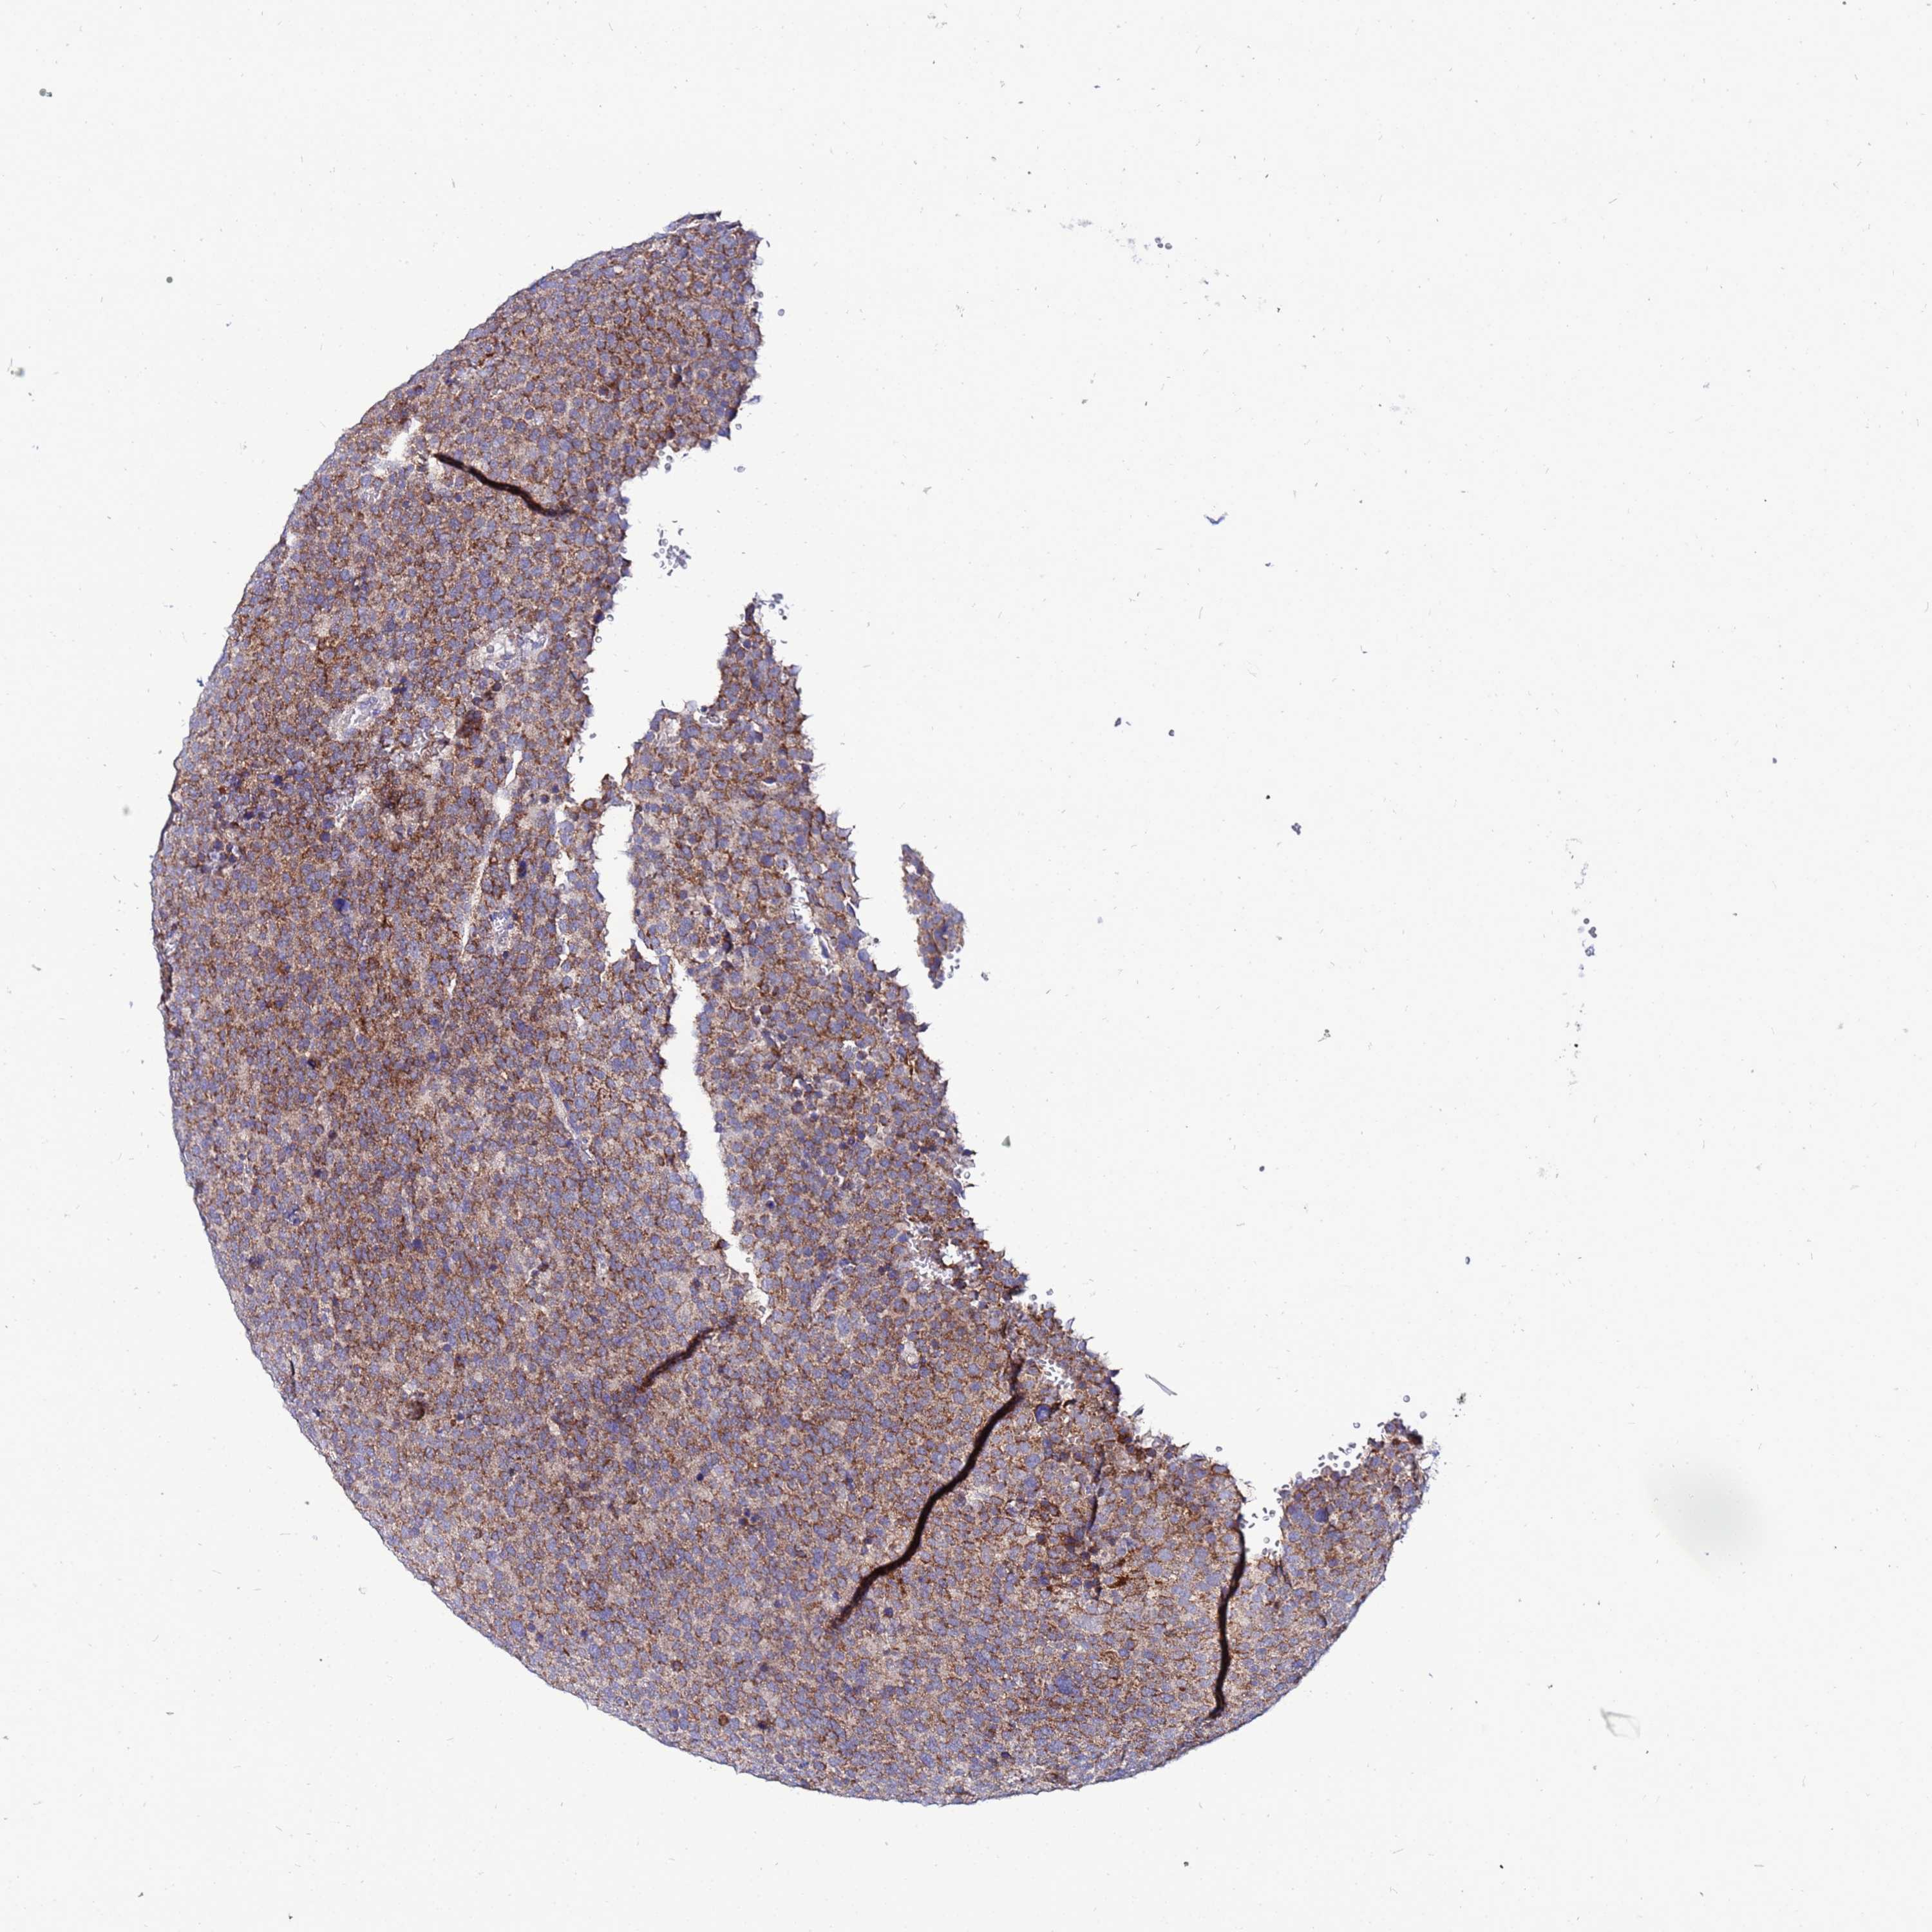

TESTIS CANCER - Protein expressioni

A mouse-over function shows sample information and annotation data. Click on an image to view it in a full screen mode. Samples can be filtered based on level of antibody staining by selecting one or several of the following categories: high, medium, low and not detected. The assay and annotation is described here.

Note that samples used for immunohistochemistry by the Human Protein Atlas do not correspond to samples in the TCGA dataset.

Antibody stainingi

Antibody staining in the annotated cell types in the current human tissue is reported as not detected, low, medium, or high, based on conventional immunohistochemistry profiling in selected tissues. This score is based on the combination of the staining intensity and fraction of stained cells.

Each image is clickable and will lead to virtual microscopy that enables deeper exploration of all samples and also displays staining intensity scores, fraction scores and subcellular localization as well as patient and tissue information for each sample.

Antibody HPA042145

Antibody HPA044987

Antibody CAB045971

Antibody CAB045972

Carcinoma, Embryonal, NOS

Seminoma, NOS